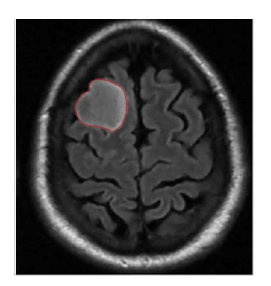

5.4 Results on brain MRI images

To achieve accurate segmentation of medical images, we have carefully tuned the parameters α, λ, and μ, which play a critical role in the performance of the DRLSE algorithm. These parameters control key aspects of the level set evolution, such as the smoothness of the contour (α), the fitting to the object boundaries (λ), and the regularization of the level set function (μ).

Using an empirical approach, we iteratively adjusted these values to obtain the best segmentation results for the images shown in Figure 10. Specifically, for brain MRIs, we found that setting α=0.5, λ=6, and μ=0.02 provided optimal segmentation results. These values effectively balance the trade-off between contour smoothness and accuracy in detecting object boundaries.

The segmentation process required several iterations to refine these parameters, highlighting the importance of adapting them to the specific characteristics of the images being analyzed. The results confirm the robustness of the DRLSE algorithm in delimiting structures in medical images.

Figure 10. Segmentation result. with the DRLSE algorithm